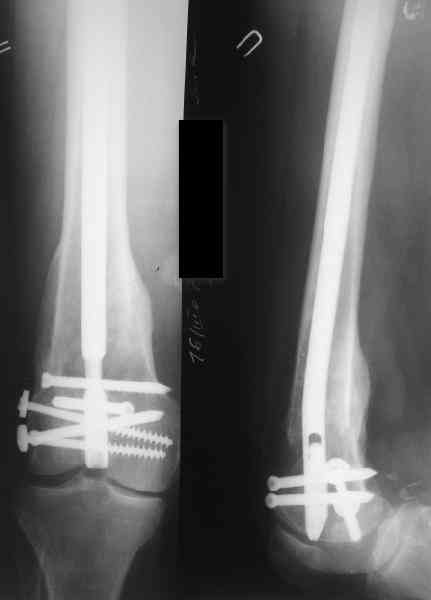

Пациенту М., 30-ти лет, 1,5 года назад в одной из московских больниц был выполнен остеосинтез бедренной кости штифтом UFN (диаметр штифта 9 мм).

К нам больной поступил с признаками ложного сустава бедренной кости, перелома

штифта и дистального блокирующего винта (images 1,2,3).

27 марта выполнено удаление блокирующих винтов (сломанный винт пришлось высверливать цапфен-бором), сломанного штифта (дистальный фрагмент удален через канал, образованный разверткой из коленного сустава - image 4),

рассверливание костно-мозгового канала, реостеосинтез штифтом UFN (при проведении штифта в дистальном отломке мы использовали поляризующий винт, диаметр штифта 10 мм). После операции в связи гемартрозом дважды (на 1 и 3 сутки) выполняли пункцию коленного сустава. Сейчас признаков скопления жидкости в полости сустава нет. Послеоперационные рентгенограммы - images 5, 6, 7.